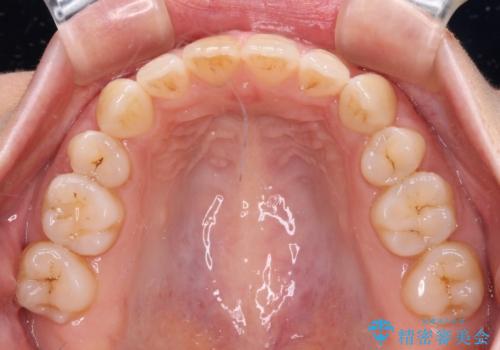

上下の前歯に隙間が空くほど上顎前歯が前に飛び出していましたが、抜歯矯正により上下前歯がぴったりと付くほど口元を引っ込めることができました。